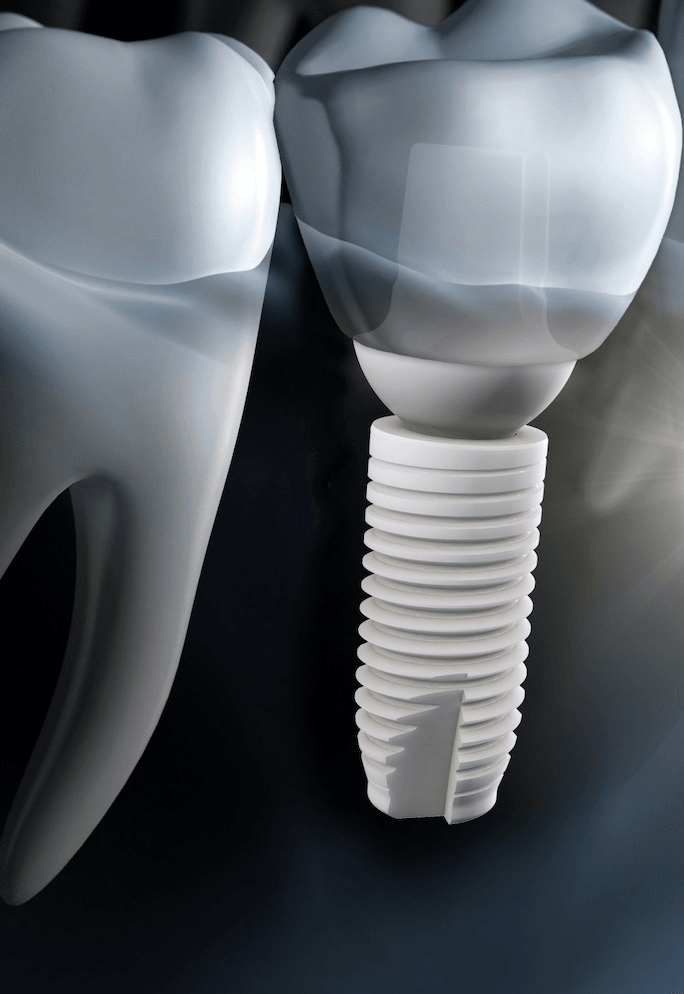

The manufacturer of this 2-piece ceramic implant

Who is Z-Systems?